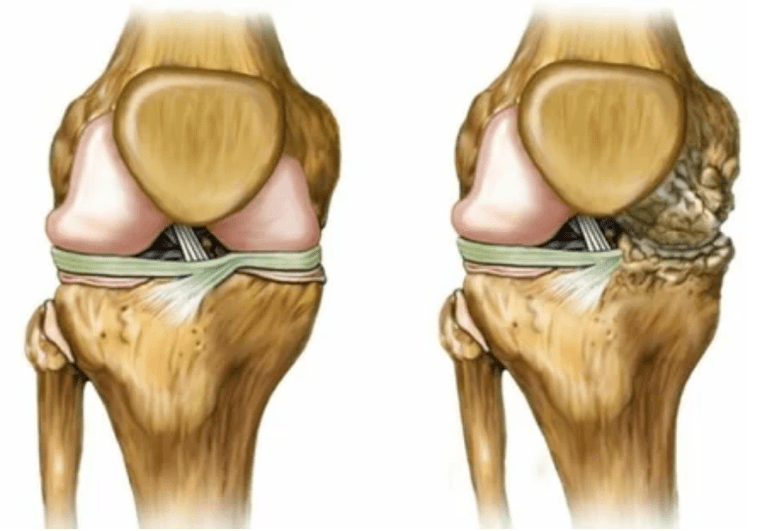

- joint deformation, cartilage has irregular shapes, stimulating curvature;

Deforming Chi.Appearing in an forgotten form of the disease, showing the complete destruction of cartilage tissue and the appearance of bone cells.In this state, the pressure on the upper and below joints increases, from which the curvature can affect the entire limb.

- The joints are completely destroyed;

- The spending is motionless, any movement becomes extremely difficult;

- The strong deformation of the joint or the whole limb.